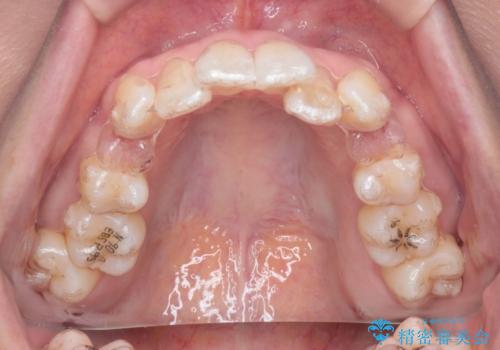

【抜歯ケース】前歯のガタガタをインビザラインで治療

- 矯正装置

- インビザライン

- 治療期間

- 2年6ヶ月

- 前歯のガタガタを主訴に来院されました。

抜歯が必要なケースでしたが、インビザラインでの治療を希望されワイヤーを使用せずに治療を完了しております。